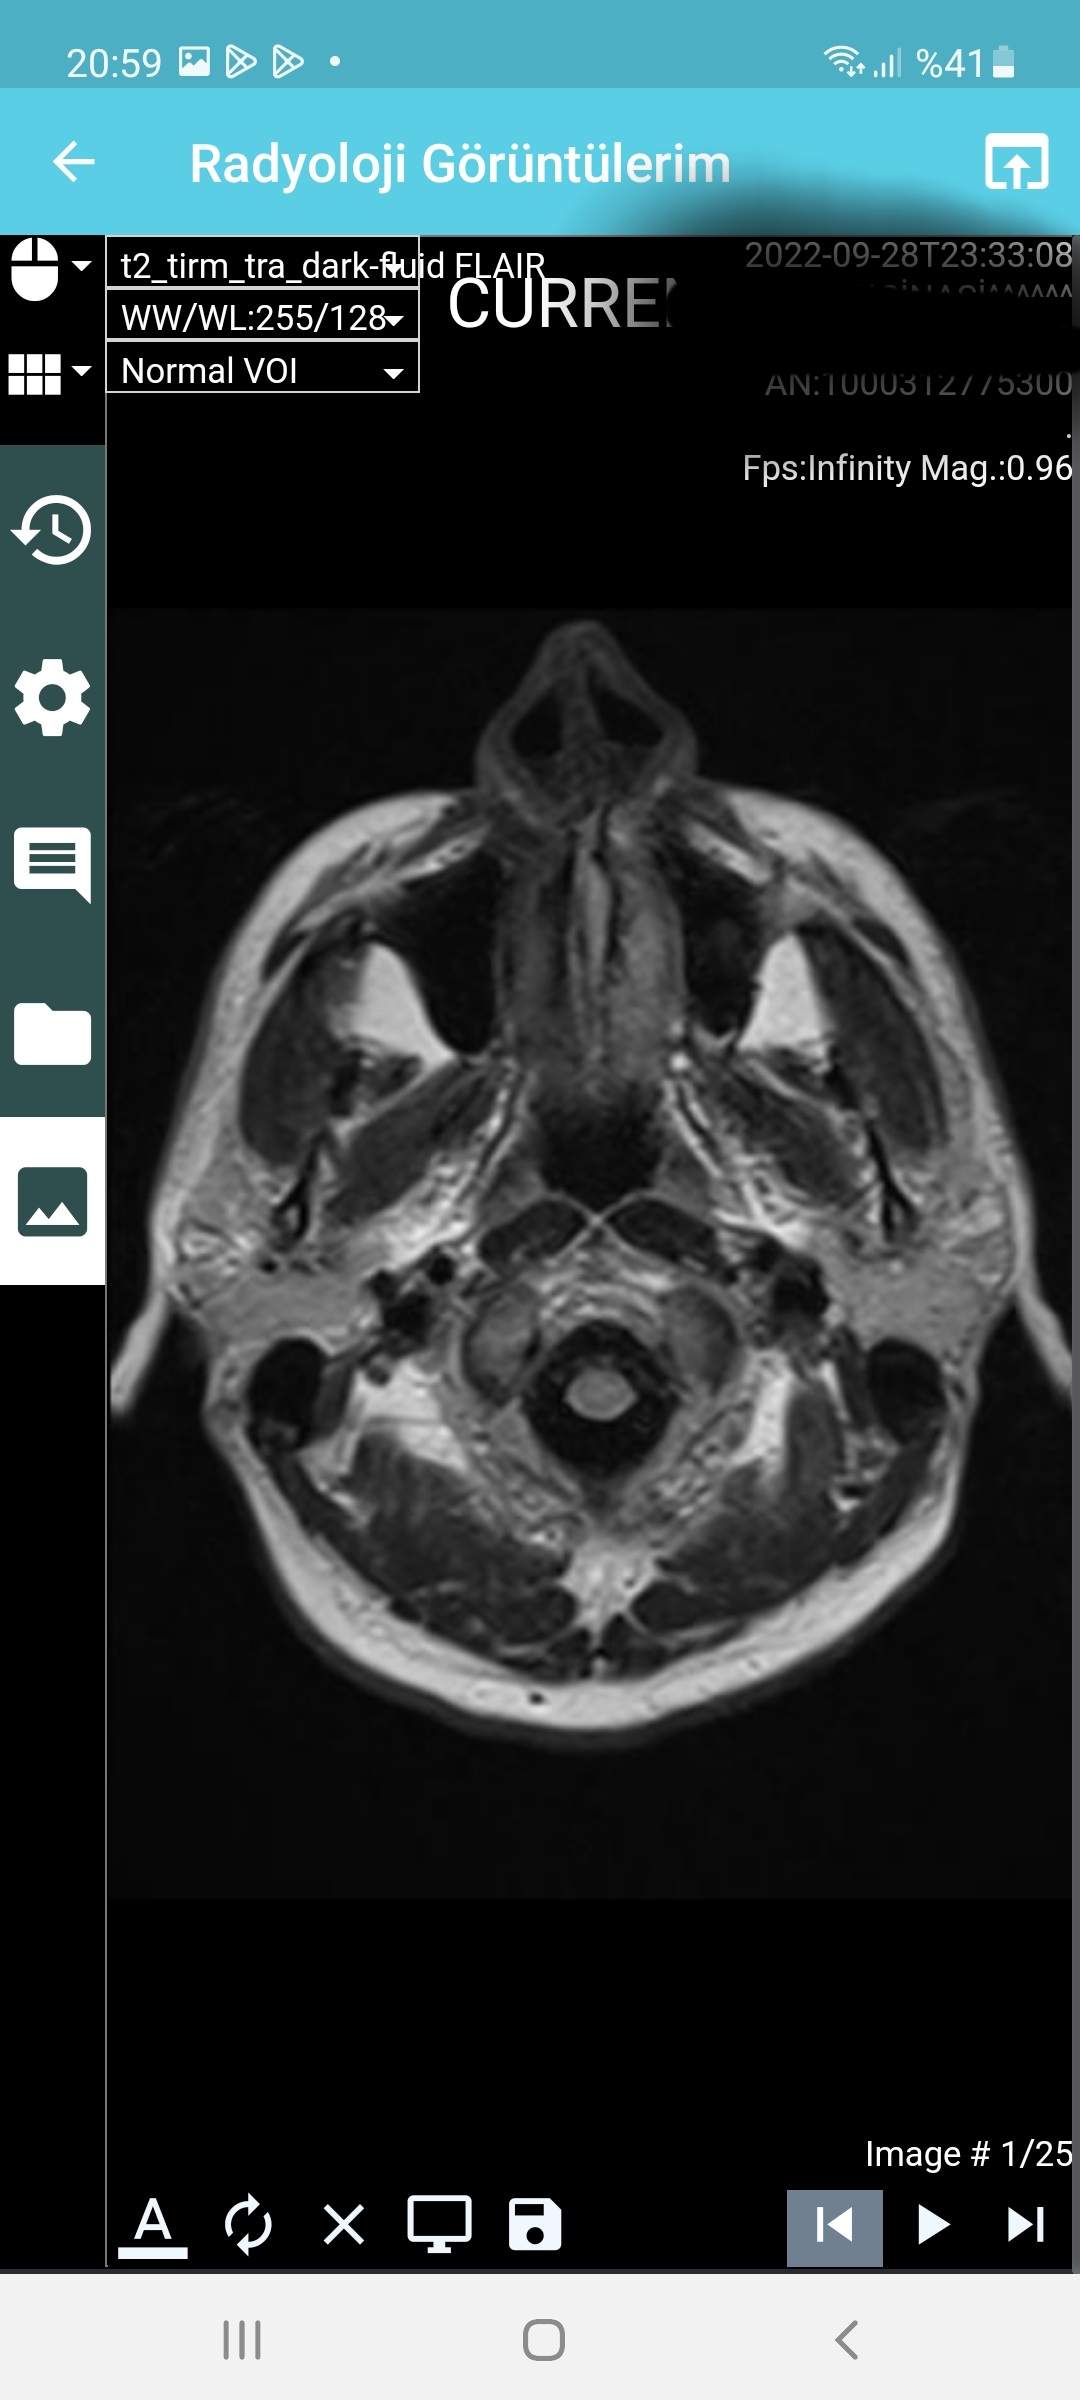

Arkadaşlar aranızda beyin emarı çektiren var mı yada bu konulardan anlayan ? Az önce emardan çıktım, emara sokan teknisyen pantolu ve kemerimi çıkartmadan emara soktu beni. Eee hani metal eşya ile girmek sakıncalı ve yasak degilmiydi? Şuan beynim şişmiş gibi acayip ağırlık var beynimde . Umarım bu emar sağlığa zararlı değildir. Radyasyon olmadığı için zararsız diyorlar ,umarım doğrudur. Hadi bunu geçtim ama o kemer umarım emar sonuçlarını etkilemez. < Bu mesaj bu kişi tarafından değiştirildi berlin007 -- 28 Eylül 2022; 23:49:8 > < Bu ileti mobil sürüm kullanılarak atıldı > |